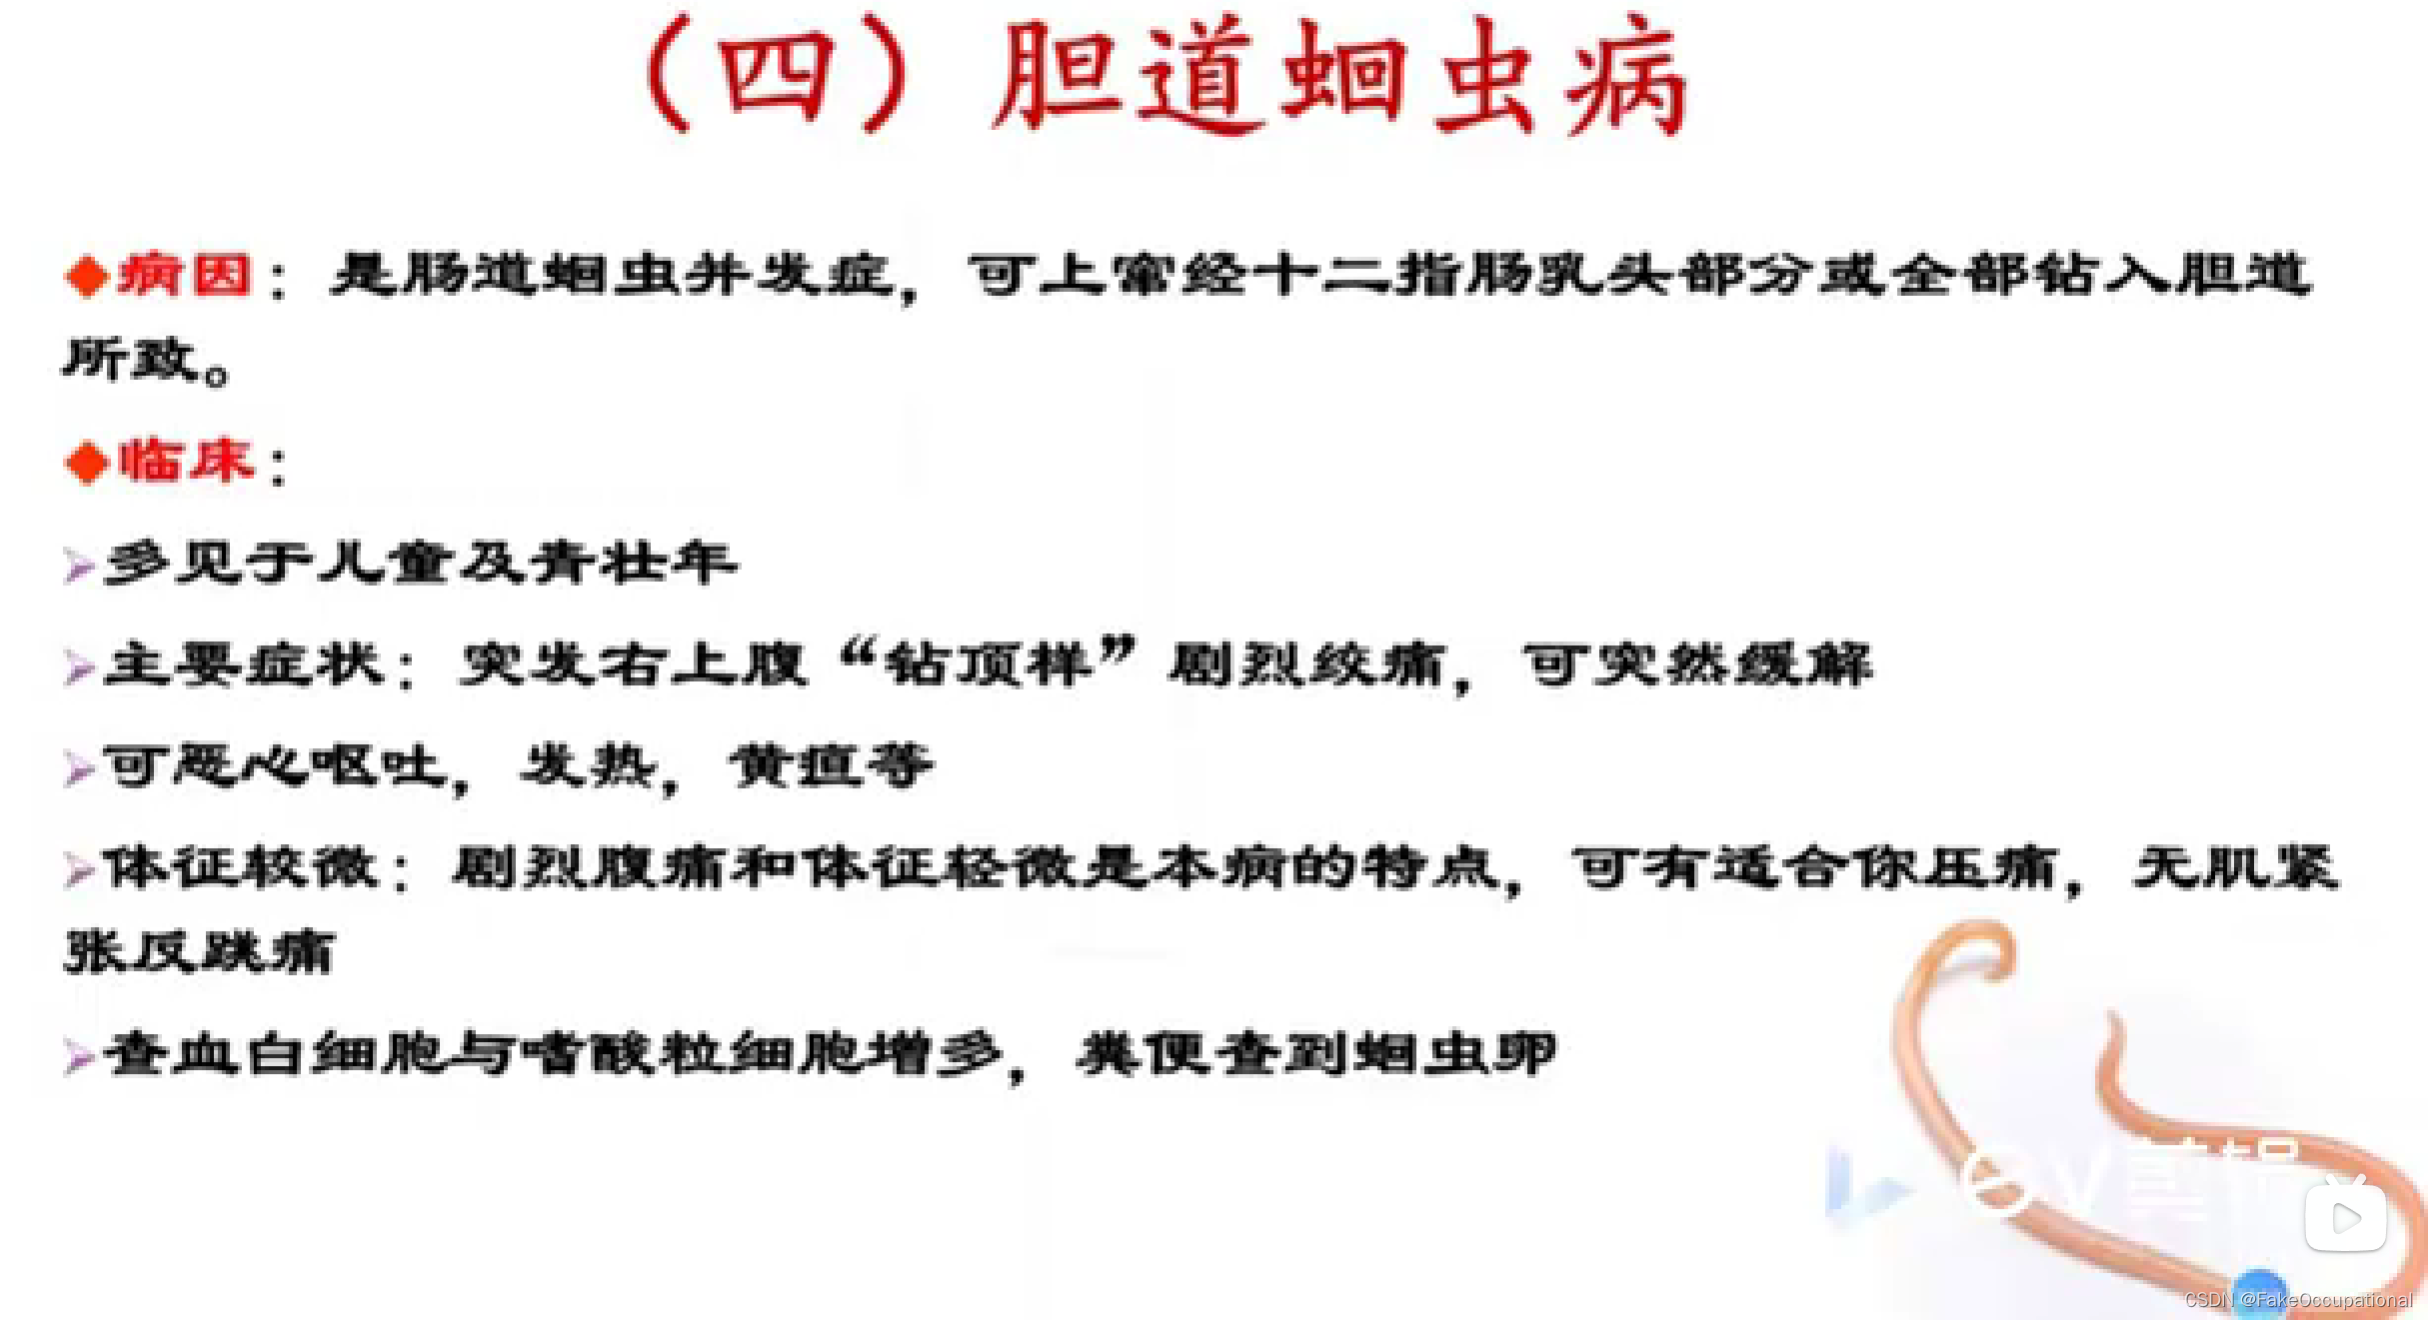

超声声像图: - 肝外胆道不同程度扩张

- 扩张胆管内可见蛔虫回纵切面为双线状长条形的平行高回声带,中央可见暗带;黄切面为“同心圆”状

- 活蛔虫可见其蠕动征象具有特异性诊断意义

- 死蛔虫:虫体萎缩,多节段性光带,中央暗带模糊或消失